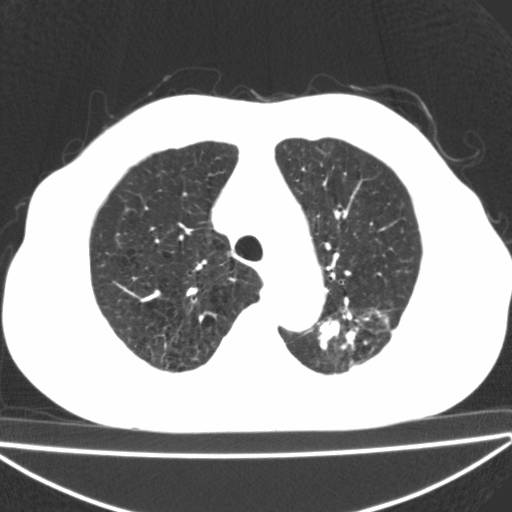

以下是引用zjzjr在2006-12-6 19:04:00的发言:[br]左肺上叶尖后段可见椭圆形高密度影,其内可见点状钙化影,周围可见卫星病灶.首先考虑结核,双侧少量胸腔积液.

以下是引用李世军在2006-12-6 19:54:00的发言:[br]左肺上叶尖后段可见椭圆形高密度影,其内可见点状钙化影,周围可见卫星病灶.首先考虑结核,双侧少量胸腔积液. [br] [br] 双肺轻度肺气肿,左肺上叶后段见多发斑片状密度增高影,周围见少许斑点状卫星病灶,双侧胸膜增厚粘连,纵隔内未见明显改变,考虑结核可能性大,请结合临床或增强扫描. [br] [br]

以下是引用13081830109在2006-12-6 19:35:00的发言:[br]左肺上叶尖后段可见椭圆形高密度影,其内可见点状钙化影,周围可见卫星病灶.首先考虑结核,双侧少量胸腔积液.

以下是引用守望可可西里在2006-12-7 0:01:00的发言:[br][quote]以下是引用zjzjr在2006-12-6 19:04:00的发言:[br]左肺上叶尖后段可见椭圆形高密度影,其内可见点状钙化影,周围可见卫星病灶.首先考虑结核,双侧少量胸腔积液.